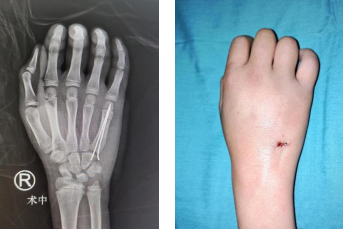

李甲主任、孙传伟医生手术团队为患儿设计了微创手术方案,微创最大的好处就是伤口小,恢复快,能满足很多患儿家长的诉求。第二天,手术进行,李甲主任、孙传伟医生手术团队术中为患儿手法复位右手第五掌骨骨折端,于右手第五掌骨基底背侧作一约0.7cm横行切口,予以切开皮肤、皮下组织,暴露第五掌骨基底部,予克氏针固定。手术非常顺利。

术中(左图)术后即刻,切口很小(右图)